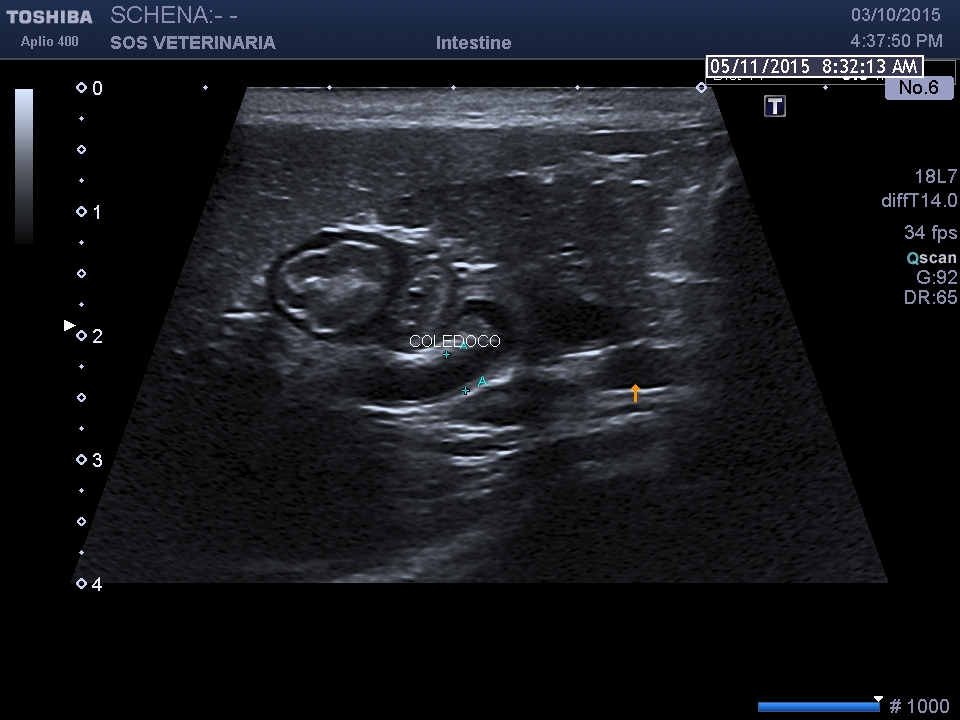

dilatazione del coledoco che decorre rettilineo

dotto biliare e vena porta dotto pancreatico ectasico  duodeno

infiltrazione diffusa perironeale di immunoblasti ,ispessimento  mucosa intestinale-dilatazione coledoco -dotti pancreatici-calcolosi biliare intra epatica ed extraepatica

Rispetto il precedente caso la paipilla duodenale  e’ normale nella forma e nelle dimensioni ,sebbene affetto da calcolosi non si visualizzano calcoli nel coledoco o a livello della papilla che giustifichino la dilatazione delle vie biliari extraepatiche e pancreatiche  ,colpisce l’ispessimento del duodeno (5 mm contro un v.n. di 2,5 )  l’ectasia del dotto pancreatico, la stasi del succo pancreatico  e la diffusa presenza di strutture nodulari isolate o confluenti riferibili tessuto linfatico iperplastico  con un infiltrato di immunoblasti predominante .

La distensione delle vie biliari e pancreatiche puo’ essere secondaria al processo infiltrativo duodenale o a complicanza infiammatoria -settica comune nella specie felina (vedi triatide)  ,le interazioni sono molteplici ,la stessa calcolosi risulta severa con aspetti di colastasi intraepatica. Questo soggetto avrebbe avuto bisogno di approfondimenti e da destinarsi ad approfondimenti oncologici ,purtroppo anche in questo caso i proprietari non hanno voluto dar seguito al naturale iter diagnostico e terapeutico che il caso imponeva .